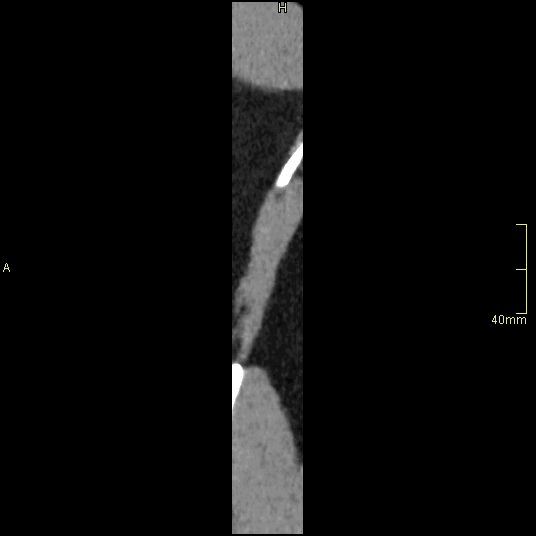

CT Lumbosacral Spine Non Contrast- Soft Tissue window (sagittal)